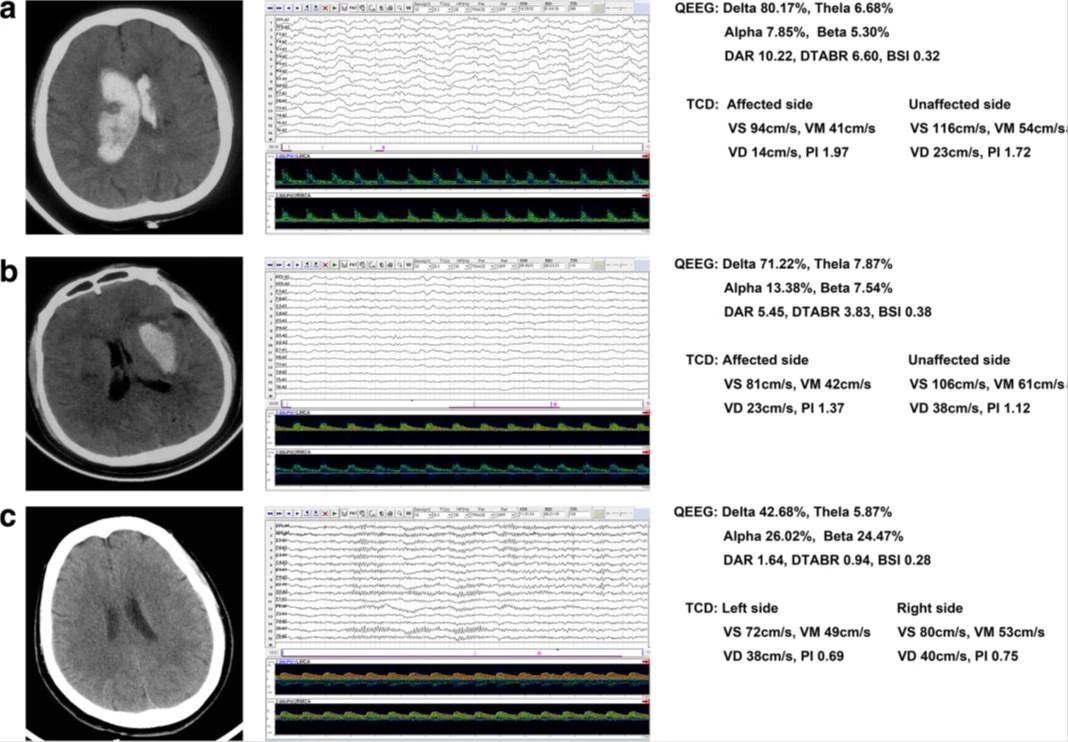

Background: Neurological deterioration after intracerebral hemorrhage (ICH) is thought to be closely related to increased intracranial pressure (ICP), decreased cerebral blood flow (CBF), and brain metabolism. Transcranial Doppler(TCD) is increasingly used as an indirect measure of ICP, and quantitative EEG (QEEG) can reflect the coupling of CBF and metabolism. We aimed to combine TCD and QEEG to comprehensively assess brain function after ICH and provide prognostic diagnosis.

Methods: We prospectively enrolled patients with severe acute supratentorial (SAS)-ICH from June 2015 to December 2016. Mortality was assessed at 90-day follow-up. We collected demographic data, serological data, and clinical factors, and performed neurophysiological tests at study entry. Quantitative brain function monitoring was performed using a TCD-QEEG recording system at the patient’s bedside (NSD-8100; Delica, China). Univariate and multivariable analyses and receiver operating characteristic (ROC) curves were employed to assess the relationships between variables and outcome.

Results: Forty-seven patients (67.3 ± 12.6 years; 23 men) were studied. Mortality at 90 days was 55.3%. Statistical results showed there were no significant differences in brain symmetry index between survivors and nonsurvivors, nor between patients and controls (all p > 0.05). Only TCD indicators of the pulsatility index from unaffected hemispheres (UPI) (OR 2.373, CI 1.299–4.335, p = 0.005) and QEEG indicators of the delta/alpha ratio (DAR) (OR 5.306, CI 1.533–18.360, p = 0.008) were independent predictors for clinical outcome. The area under the ROC curve after the combination of UPI and DAR was 0.949, which showed better predictive accuracy compared to individual variables.

Conclusions: In patients with SAS-ICH, multimodal neuromonitoring with TCD combined with QEEG indicated that brain damage caused diffuse changes, and the predictive accuracy after combined use of TCD-QEEG was statistically superior in performance to any single variable, whether clinical or neurophysiological。